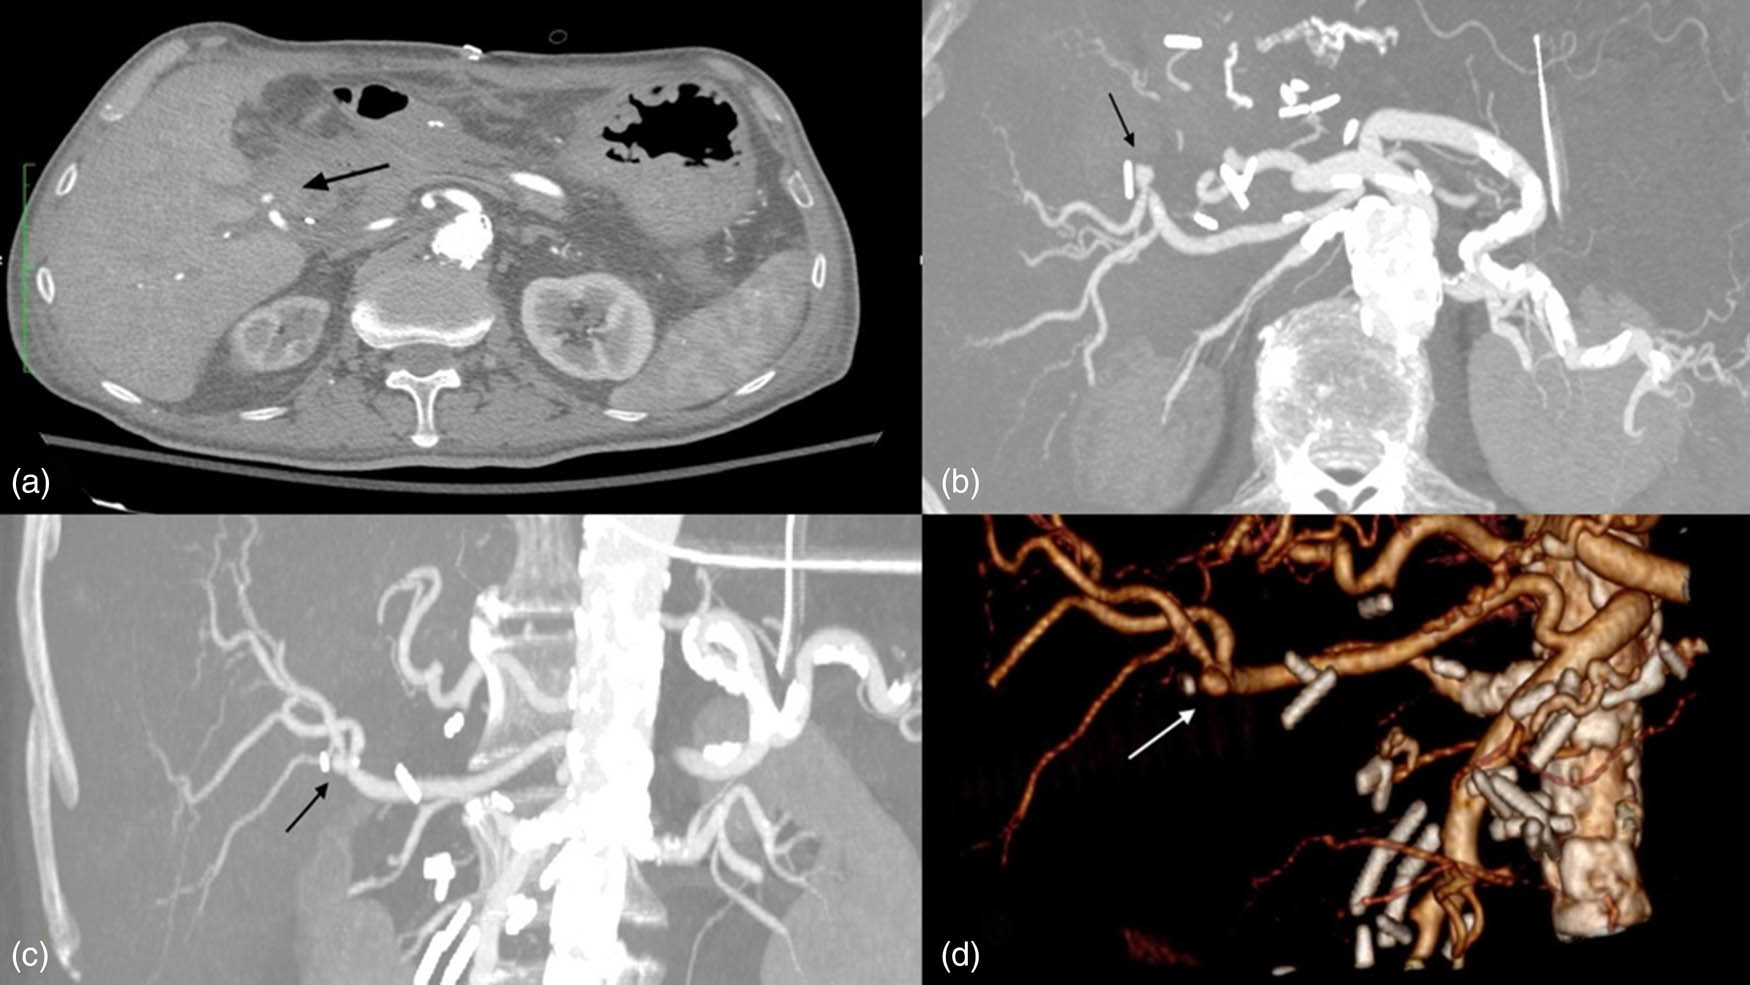

However, 2 days later, a more severe episode of gastrointestinal hemorrhage occurred. An urgent CTA was performed, which identified an aberrant right hepatic artery arising from the SMA and a pseudoaneurysm at its bifurcation (Figure 1) in close proximity to the hepaticojejunal anastomosis with a maximum diameter of 8 mm, without evidence of contrast extravasation (Figure 2).

CTA. Arrows show hepatic artery pseudoaneurysm: (a) axial view, (b) axial MPR, (c) coronal MPR, (d) 3d reconstruction.